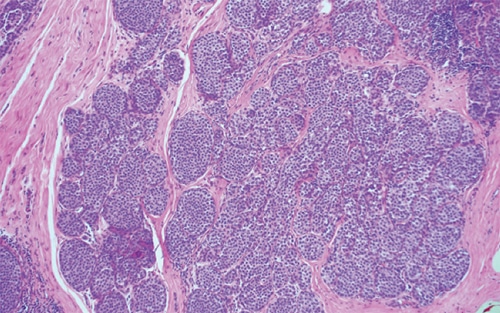

Prototypical morphology

- Distended lobules (Figure 5-10) are seen filled with loosely cohesive, monomorphic cells with low-grade nuclei.

- ALH involves less than 50% of acini in a terminal ductal lobular unit (more than this constitutes LCIS).

Special studies

- Absence of membranous E-cadherin staining (in contrast to ductal proliferations).

- Absence of nuclear beta catenin (in contrast to ductal proliferations).

- Cytoplasmic p120 staining (as opposed to membranous staining in ductal lesions).

Treatment and prognosis

- Treatment options include surveillance, chemoprevention with tamoxifen, and excision.

- ALH confers 4–5× increase in relative risk for subsequent breast cancer (including both ductal and lobular types).